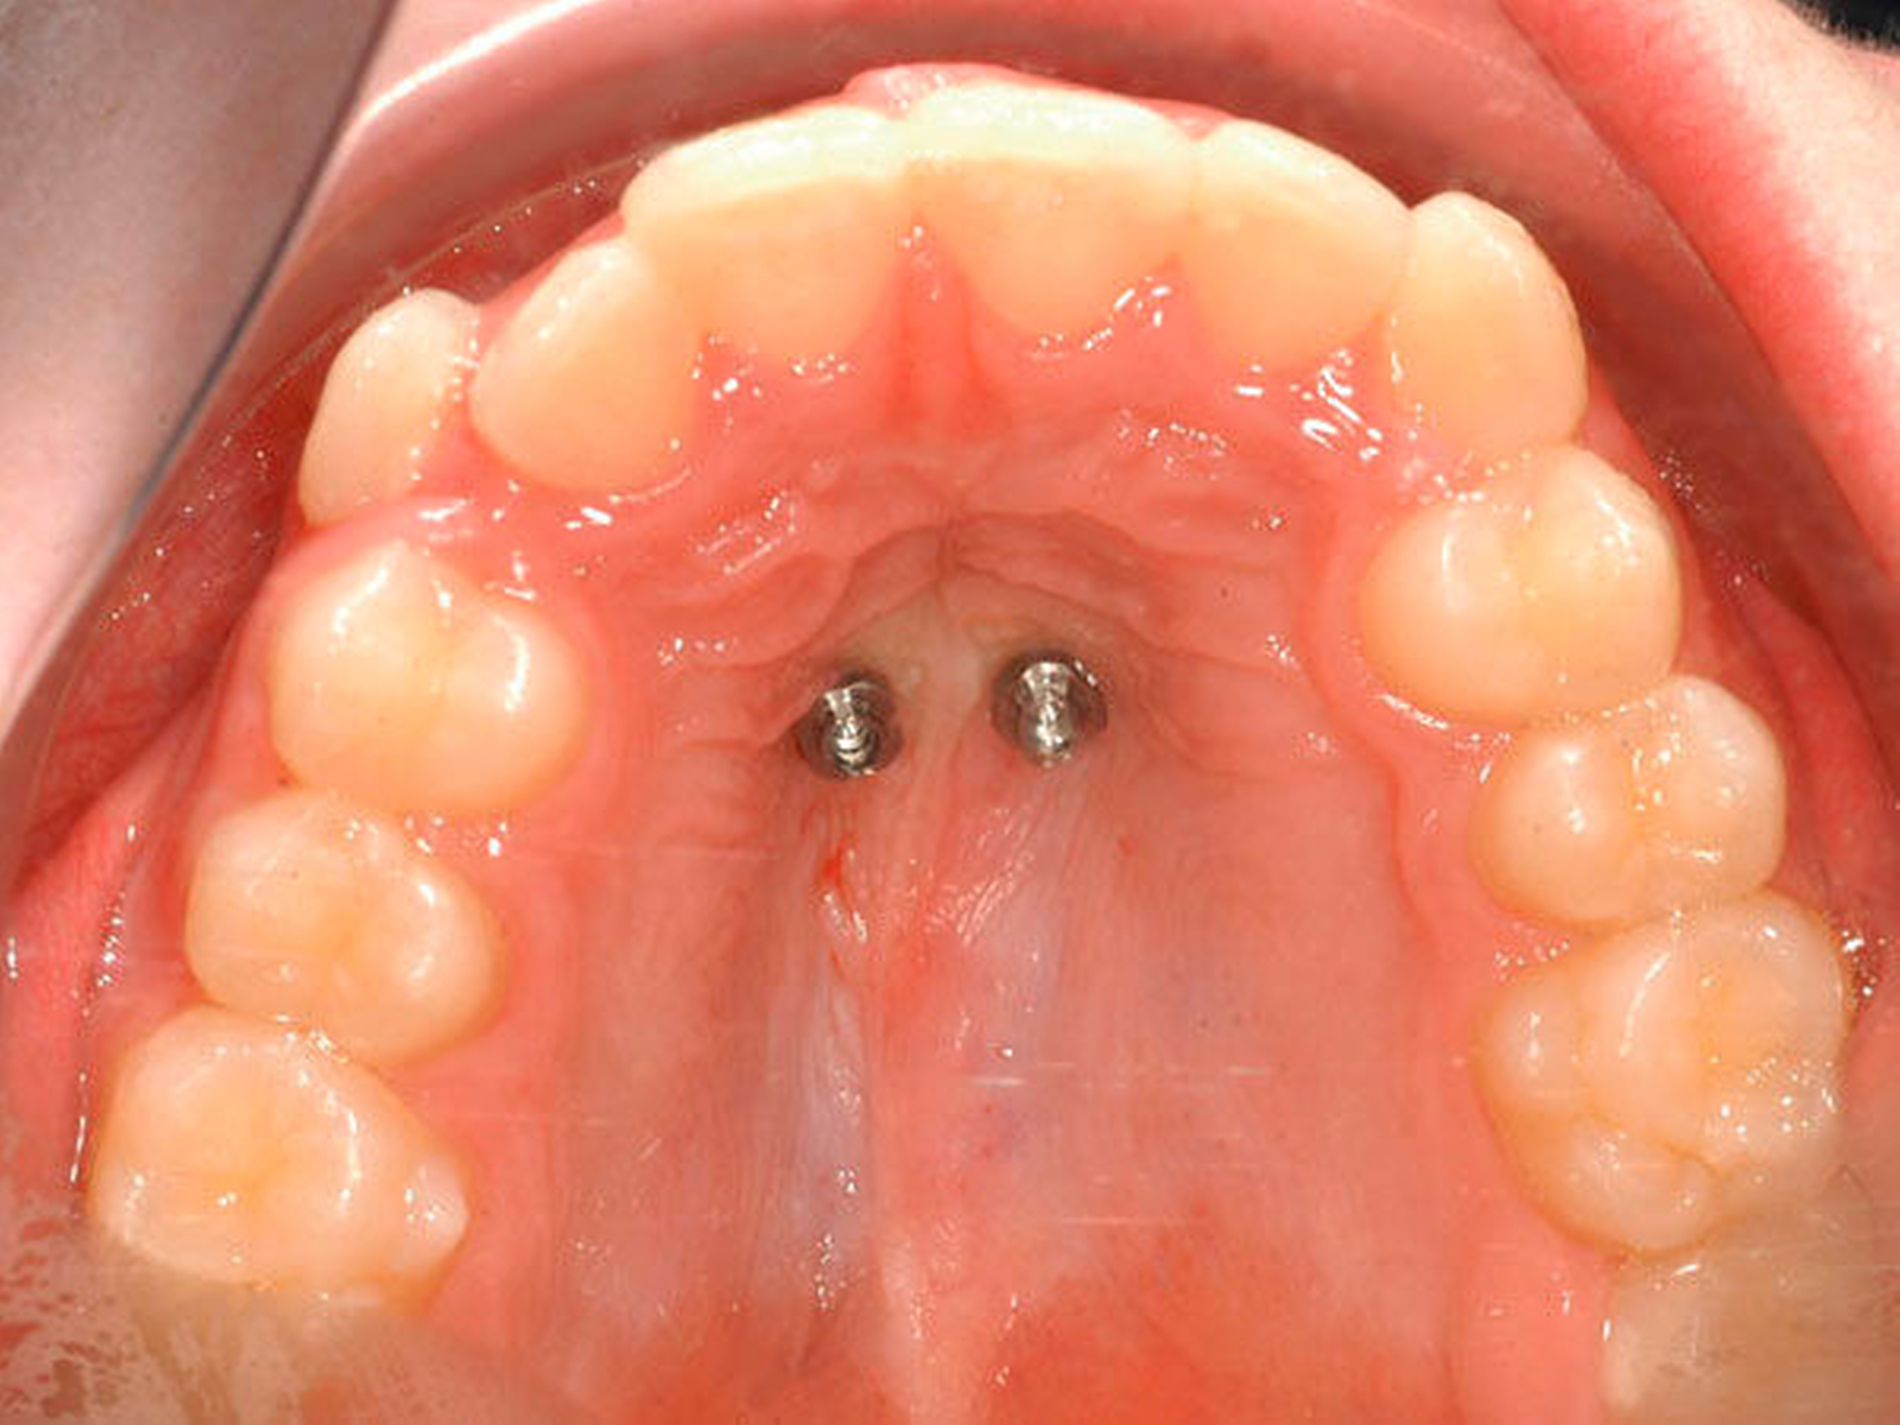

Das Prinzip einer CAD/CAM-gesteuerten Insertion wird anhand einer zehnjährigen Patientin mit einem Platzmangel für die oberen Eckzähne dargestellt (Abbildungen 4a, 4b). Die Behandlung begann mit dem Anpassen von Molarenbändern und einem Silikon-Abdruck des Oberkiefers, der mit dem FRS an das zahntechnische Labor gesendet wurde und dort mit dem FRS der Patientin überlagert wurde. So konnten geeignete Insertionsstellen virtuell geplant werden (Abbildungen 1, 2a, 2b). Nach Rücksprache mit dem Behandler bezüglich der Mini-Implantatpositionen erfolgte die Herstellung der Insertionsschablone (Abbildung 3). Parallel dazu wurde auch der Beneslider [Wilmes, 2010] hergestellt, der zusammen mit der Insertionsschablone geliefert wurde (Abbildung 5). Mithilfe der Insertionsschablone konnten die Mini-Implantate und der Beneslider im selben Termin eingesetzt werden (Abbildungen 6, 7a, 7b). Nach 10 Monaten Distalisierung waren die Molaren in der Zielposition und es war ausreichend Platz für die Eckzähne vorhanden (Abbildungen 8a, 8b), so dass Brackets für die zweite Phase der Behandlung eingesetzt werden konnten. Die Multibracket-Apparatur (Abbildung 9) konnte nach 12 Monaten entfernt werden (Abbildungen 10, 11).